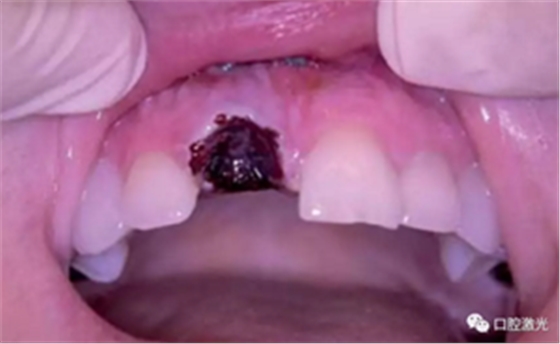

术后即刻